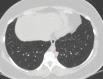

The coronavirus disease 2019 (COVID-19) pandemic is a global health care emergency. Although reverse-transcription polymerase chain reaction testing is the reference standard method to identify patients with COVID-19 infection, chest radiography and CT play a vital role in the detection and management of these patients. Prediction models for COVID-19 imaging are rapidly being developed to support medical decision making. However, inadequate availability of a diverse annotated data set has limited the performance and generalizability of existing models. To address this unmet need, the RSNA and Society of Thoracic Radiology collaborated to develop the RSNA International COVID-19 Open Radiology Database (RICORD). This database is the first multi-institutional, multinational, expert-annotated COVID-19 imaging data set. It is made freely available to the machine learning community as a research and educational resource for COVID-19 chest imaging. Pixel-level volumetric segmentation with clinical annotations was performed by thoracic radiology subspecialists for all COVID-19-positive thoracic CT scans. The labeling schema was coordinated with other international consensus panels and COVID-19 data annotation efforts, the European Society of Medical Imaging Informatics, the American College of Radiology, and the American Association of Physicists in Medicine. Study-level COVID-19 classification labels for chest radiographs were annotated by three radiologists, with majority vote adjudication by board-certified radiologists. RICORD consists of 240 thoracic CT scans and 1000 chest radiographs contributed from four international sites. It is anticipated that RICORD will ideally lead to prediction models that can demonstrate sustained performance across populations and health care systems.